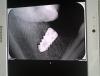

Phony_slob Опубликовано 30 июня, 2013 Поделиться Опубликовано 30 июня, 2013 Что посоветуете делать? Точить седьмой или попробовать выпрямить ортодонтически? Если второй вариант, сколько это может занять времени? Ссылка на комментарий

red_butler Опубликовано 30 июня, 2013 Поделиться Опубликовано 30 июня, 2013 Этот снимок имеет геометрические искажения, поставте формирователь. Если позиция делает протезирование невозможным или заведомо провальным, я бы подключил ортодонта, причем толкать можно от Импланта 4 Ссылка на комментарий

Luger Опубликовано 3 июля, 2013 Поделиться Опубликовано 3 июля, 2013 Что посоветуете делать? Точить седьмой или попробовать выпрямить ортодонтически? Если второй вариант, сколько это может занять времени?ТМА Абатмент и винтовая фиксация..как более быстрое решение вопроса. Ссылка на комментарий

Plombir Опубликовано 16 июля, 2013 Поделиться Опубликовано 16 июля, 2013 Не изменив ориентацию 4.7, не избежать кармана со всеми вытекающими 1 Ссылка на комментарий